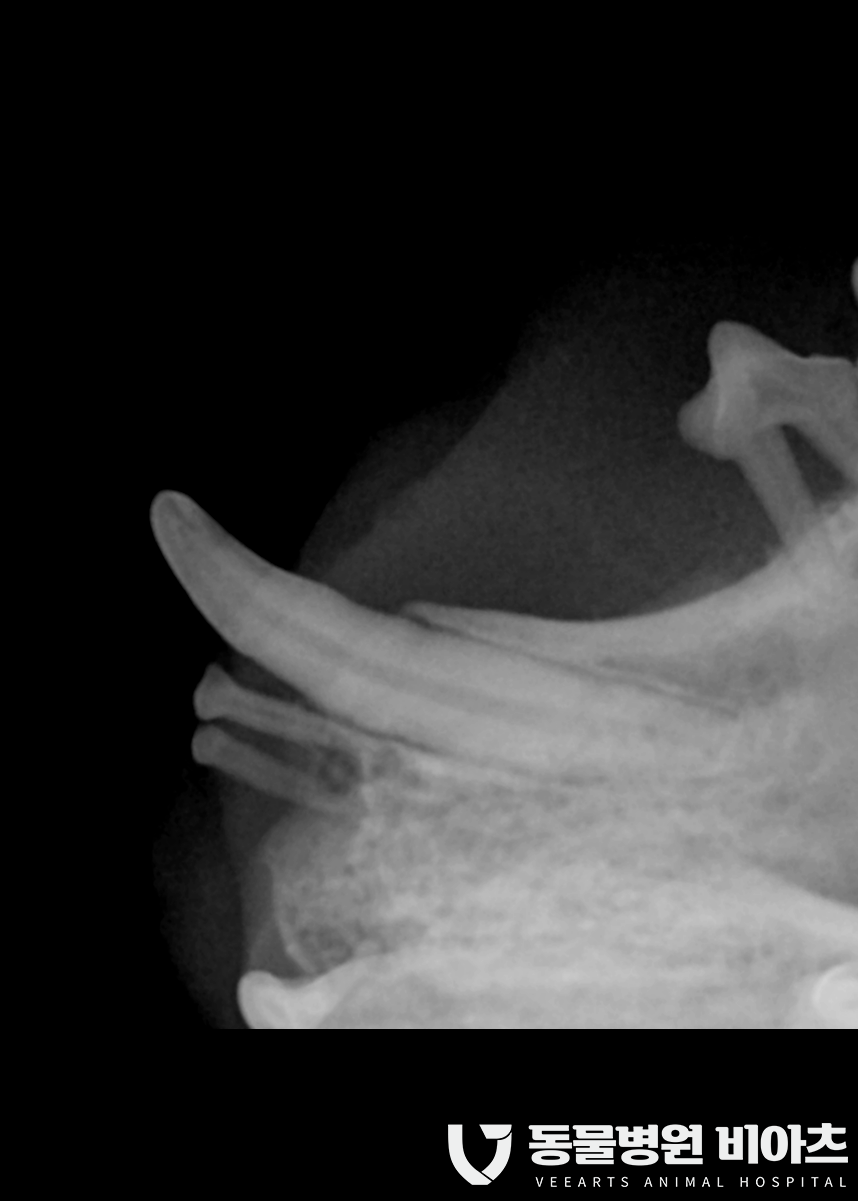

수술 전 치과 엑스레이를 통해

최소 10컷 이상의 촬영을 합니다.

치과 엑스레이는 보통 발치 전 발치 후

모두 찍습니다.

엑스레이 촬영을 통해 뿌리까지 완벽히 제거가

되었는지 확인을 해야 하기 때문입니다.

그냥 사진만 봐도

상태가..

많이 안 좋습니다..

혀에도 염증이.

얼마나 고통스러웠을까요?